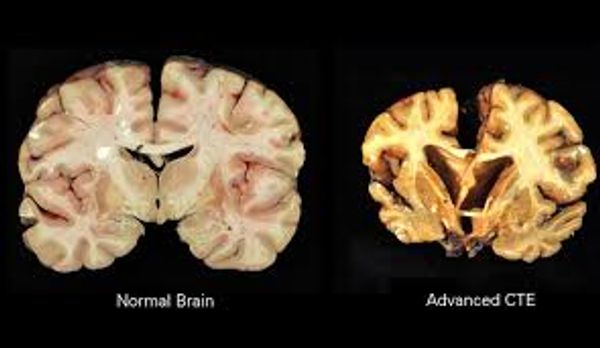

He believes he is suspected CTE after all the testing and symptoms.

After suffering from cognitive issues since 1998 Corey fully retired in 2022 and started seeing top neurologists and getting tested. He went for evaluation at UT Health San Antonio-Glenn Briggs Institute for Alzheimer's and Neuro Degenerative diseases CTE Evaluation Center. He was diagnosed Traumatic Encephalopathy Syndrome (TES), probable CTE.